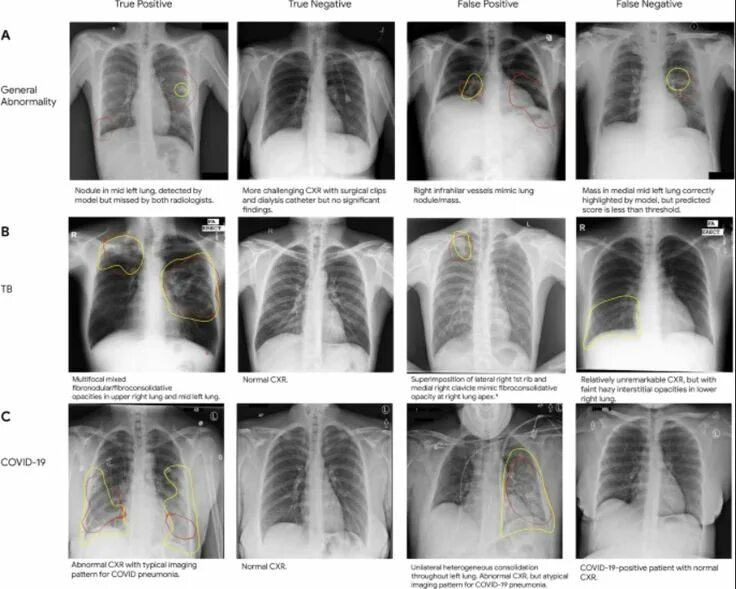

Normal abnormal